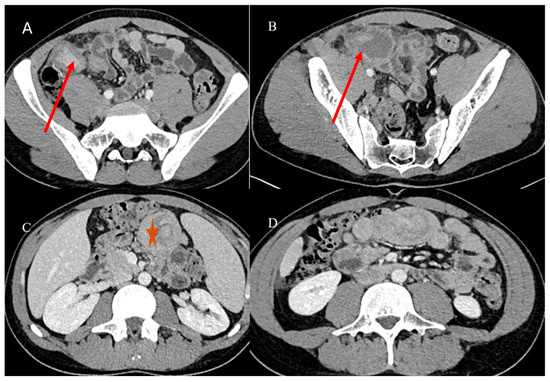

- Brogna, B.; Imbriani, G.C.; Forte, N.R.; Schettino, M.; Morelli, R.; Venditti, M.; Manganiello, C.; Biondo, F.G. Multifocal gastrointestinal stromal tumor: A case report with CT, surgical, and histopathologic correlation. Radiol. Case Rep. 2019, 14, 962–966. [Google Scholar] [CrossRef] [PubMed]